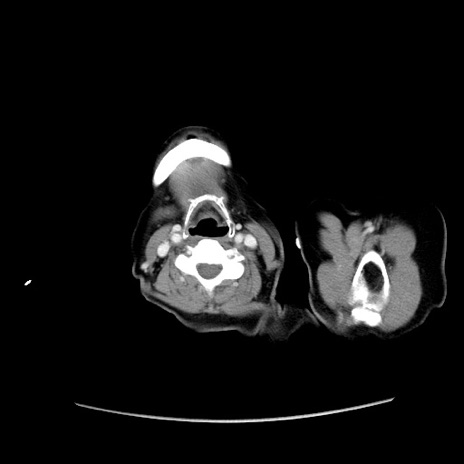

症例19(横断像)

【症例】80歳代女性

【主訴】下腹部痛

【現病歴】約8時間前より下腹部痛の出現あり、救急外来受診。

【既往歴】両側付属器切除

【身体所見】意識清明、下腹部正中に手術痕あり、その部位に一致して圧痛と反跳痛あり。腸蠕動音は亢進。

【データ】WBC 9300、CRP 0.15